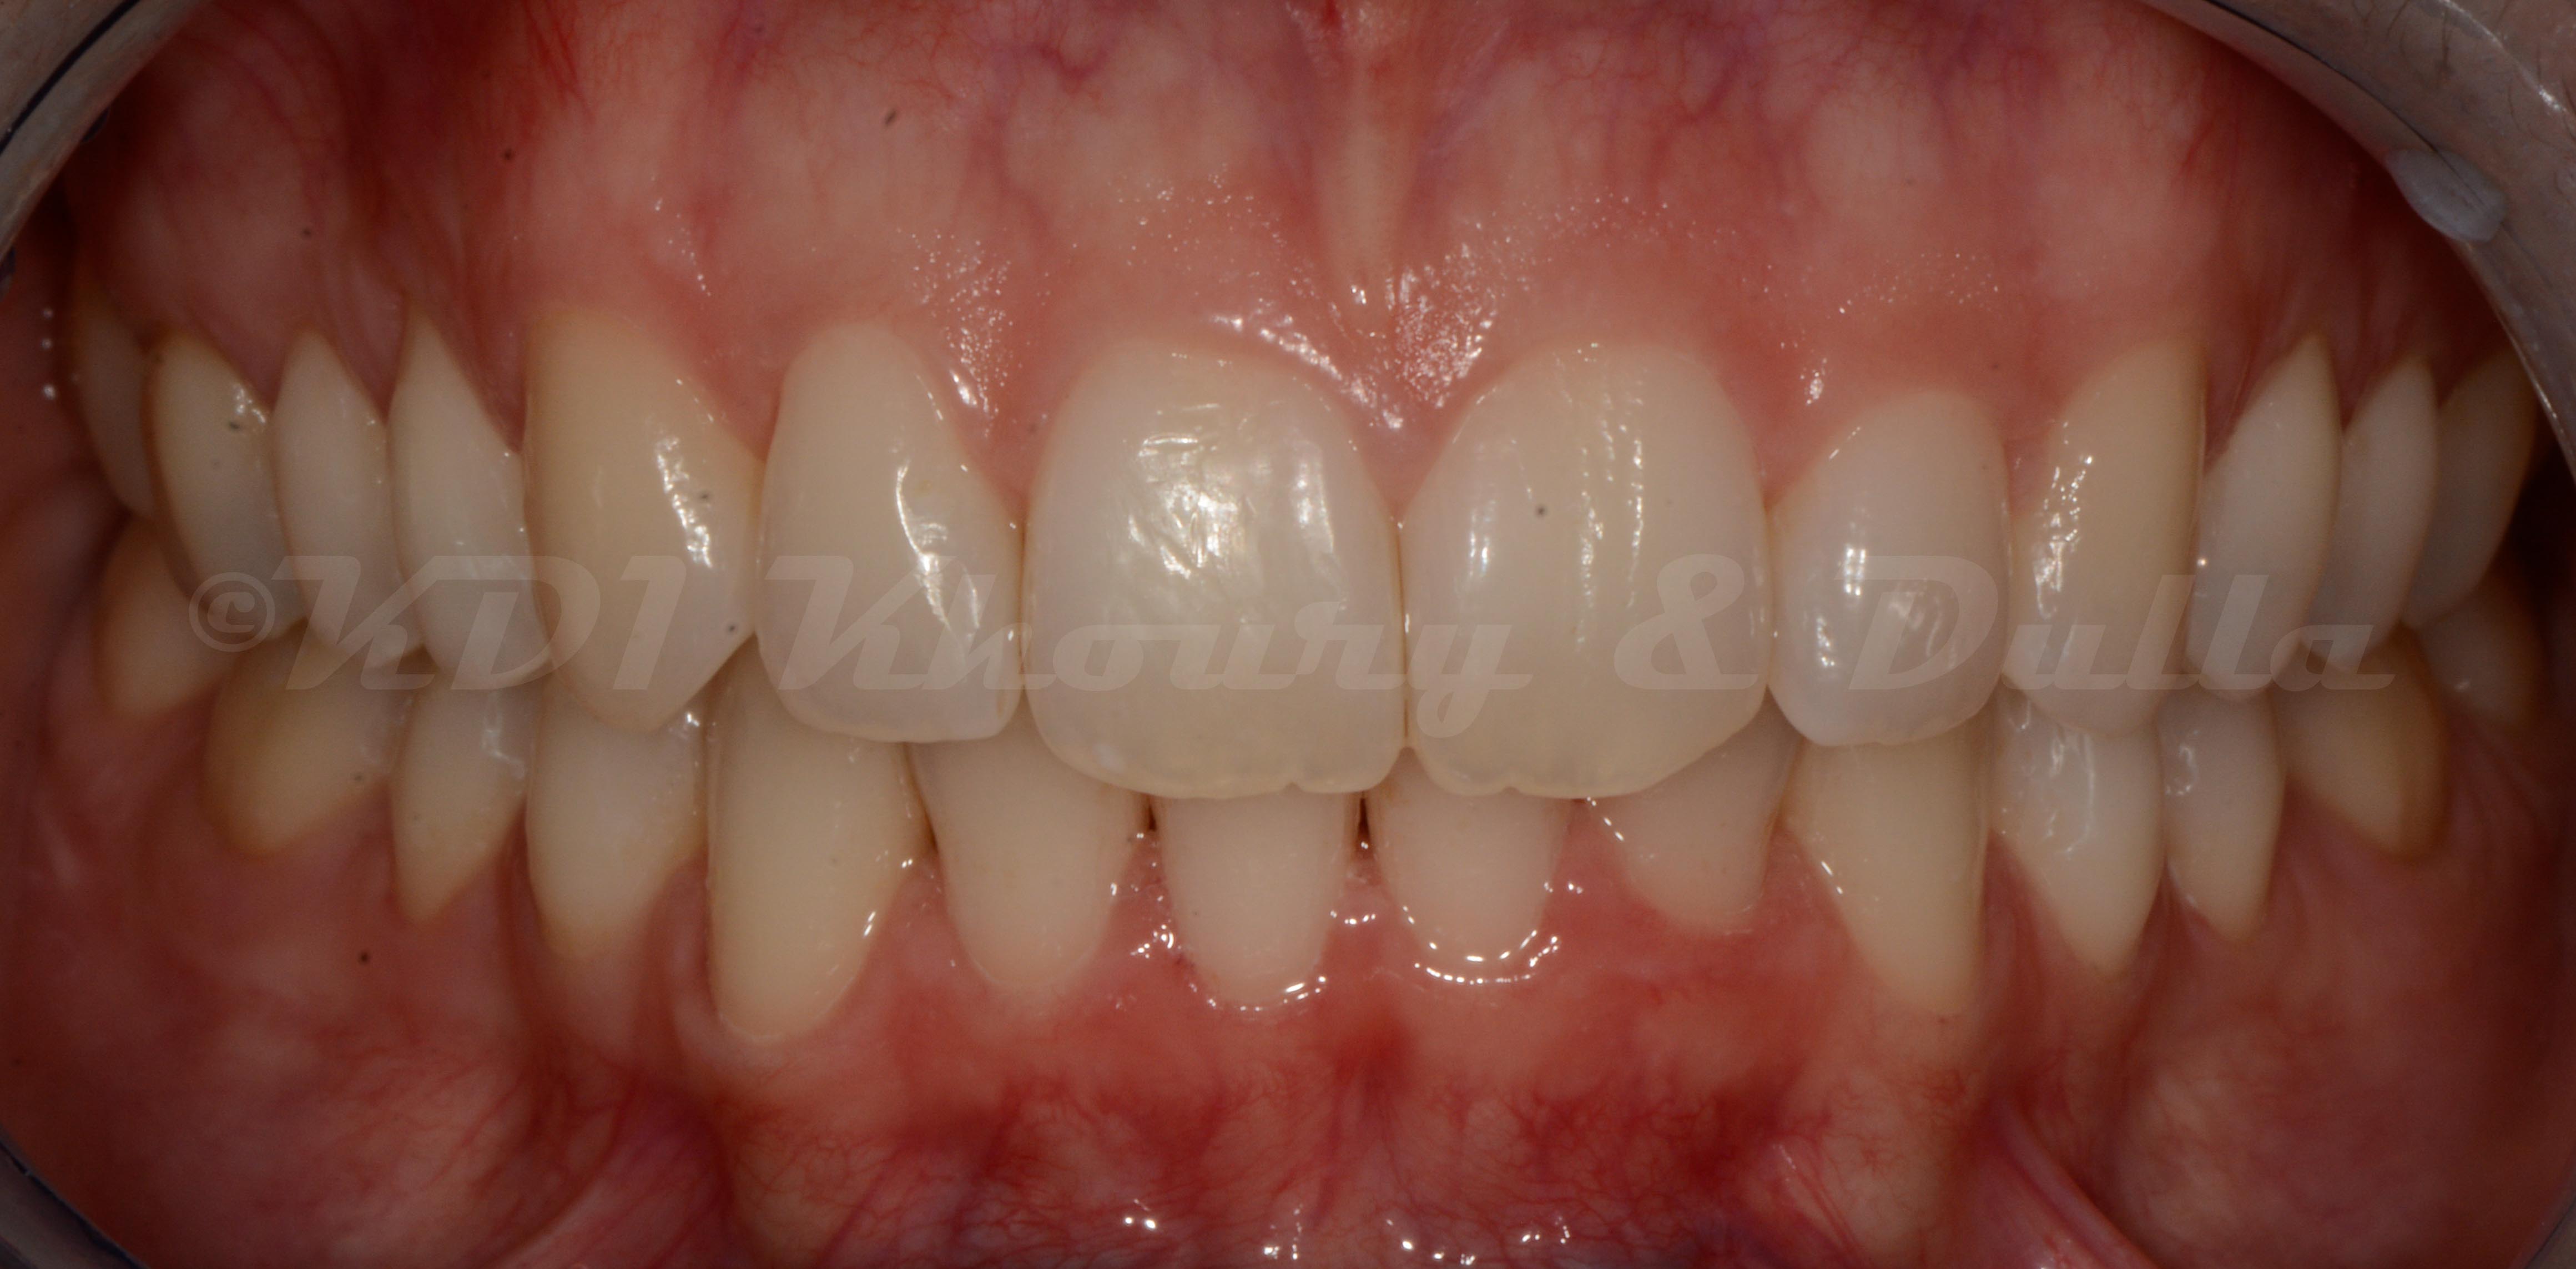

Cas #1 – Traitement avec des bagues, deuxièmes prémolaires et dent de sagesse supérieures ectopiques.